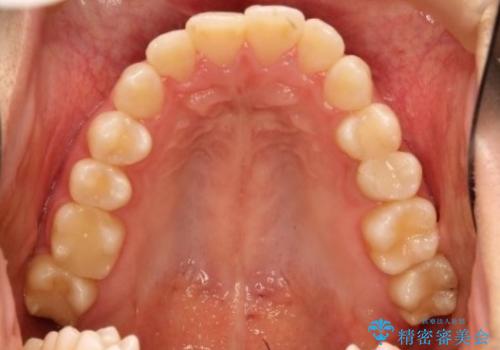

- 前歯の凸凹を主訴に来院されました。

非抜歯の範囲でできるだけ前歯を下げることを希望されたため、IPRと臼歯部の遠心移動を行い治療を行いました。当初はインビザラインで治療を行っておりましたが、使用時間を十分に確保できないことで途中からワイヤーを使用しております。